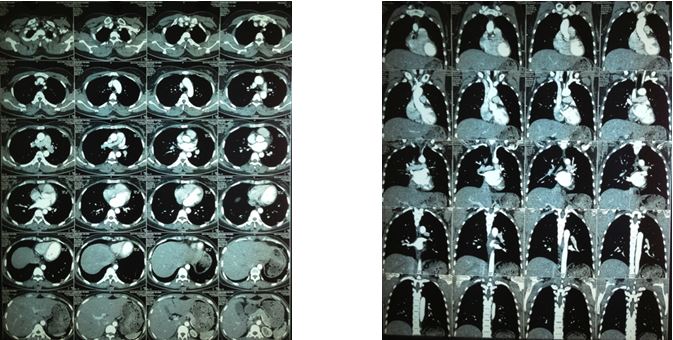

1. Chụp cắt lớp vi tính 64 dãy lồng ngực sau 5 tháng điều trị:

• Không thấy bất thường trên phim cắt lớp vi tính 64 dãy lồng ngực

• Không thấy hạch trung thất

Hình 10: Hình ảnh cắt lớp vi tính 64 dãy lồng ngực sau 5 tháng điều trị không thấy tổn thương ở phổi và không phát hiện hạch trung thất.